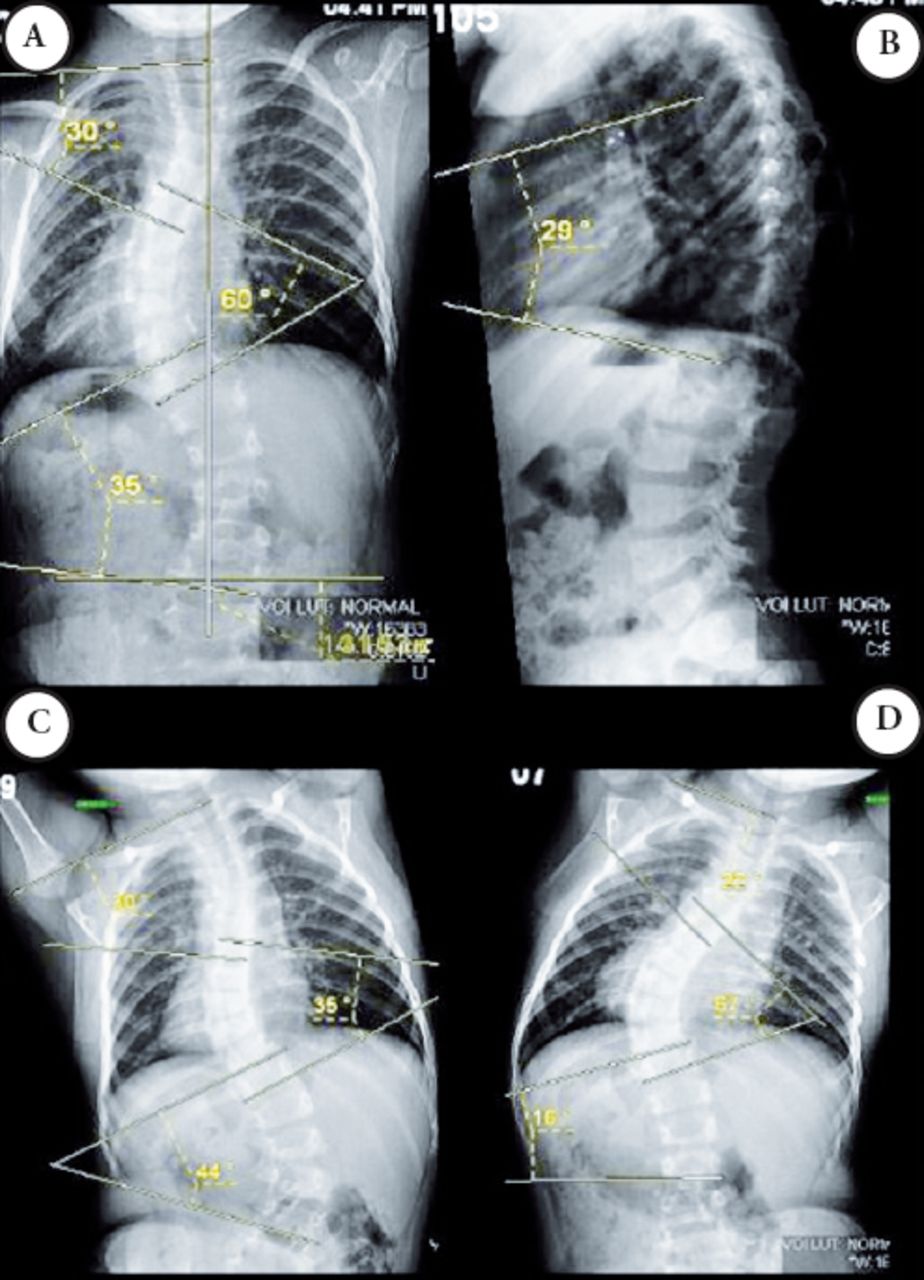

Growing Rods for Early Onset Scoliosis and Its Magic Rods For Scoliosis These growing rods use a magnetic remote. In this treatment system, a spine surgeon will. In this review, we examine the results from clinical, radiological and explant studies following the use of magec, in the context of other. Magec growing rods are a new surgical treatment for children with severe spinal deformities that uses implantable rods and an external remote.. Magic Rods For Scoliosis.

Example of a patient with an early onset idiopathic scoliosis treated Magic Rods For Scoliosis Magec growing rods are a new surgical treatment for children with severe spinal deformities that uses implantable rods and an external remote. Magec (magnetic expansion control) growing rods are used to treat children with significant spinal curvature resulting from scoliosis. After the initial procedure to implant the rod,. In this treatment system, a spine surgeon will. These growing rods use. Magic Rods For Scoliosis.